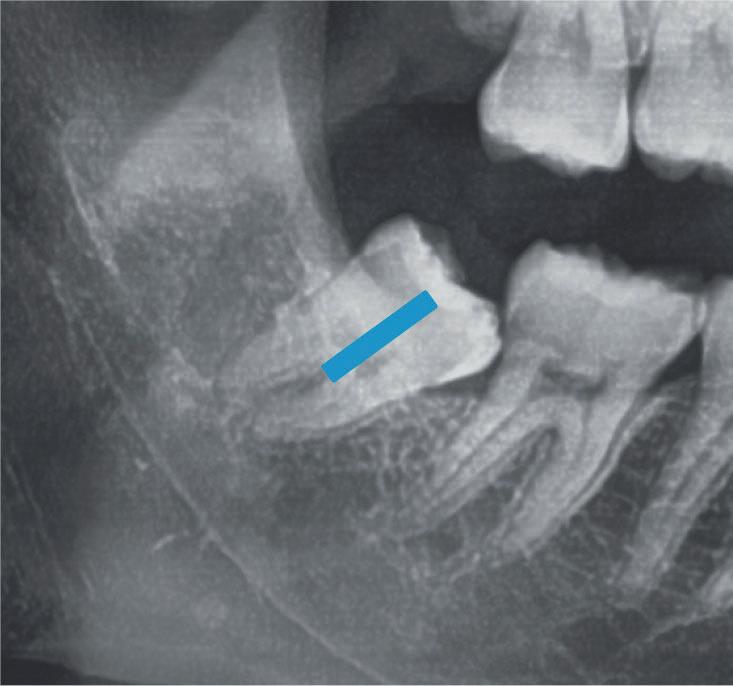

Dalla radiografia (Fig. 166) sembrava che il dente avesse due radici separate, quindi è stato eseguito un taglio orizzontale utilizzando il manipolo dritto per sezionare il dente a metà. Tuttavia, la corona si è frat-

turata poiché in realtà le radici erano unite e il dente non è stato sezionato completamente.